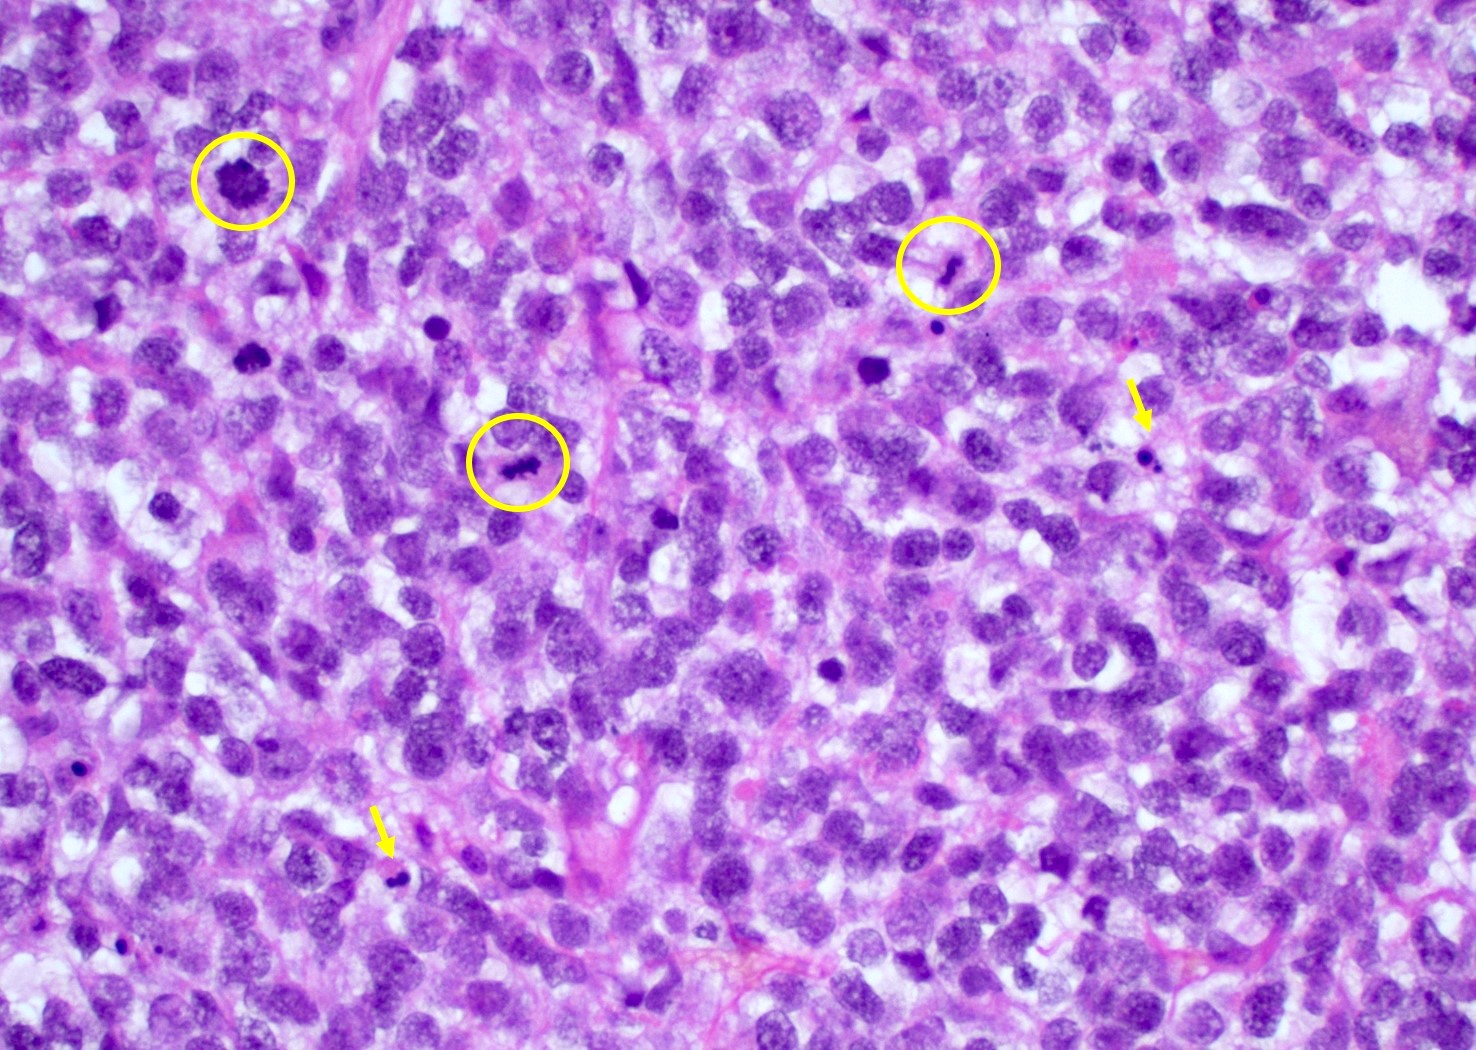

Microscopic (histologic) description

- Infiltrating, hypercellular astrocytic neoplasm often with hyperchromatic, elongated nuclei and irregular nuclear membranes

- Typically mitotically active, though not required if molecular criteria are met

- Microvascular proliferation or necrosis is required for a histologic diagnosis of GBM

- Microvascular proliferation: multilayered, small caliber vessels with glomeruloid appearance (J Neuropathol Exp Neurol 1992;51:488)

- Necrosis: can be geographic or pseudopalisading with neoplastic cells surrounding central necrosis

- Greater association of thrombosis and necrosis in IDH wild type GBM than in IDH mutant grade 4 astrocytomas (Acta Neuropathol 2016;132:917)

- Variable cell morphology: undifferentiated / primitive neuronal cells, astrocytic, gemistocytic, oligodendroglial-like, small cell, lipidized, granular, epithelioid, giant cells, mesenchymal metaplasia and epithelial metaplasia

- Primitive neuronal cells (embryonal): markedly increased cellularity composed of cells with high N/C ratio, brisk mitotic activity with apoptotic bodies, nuclear molding, sometimes with neuroblastic rosettes

- Typically has conventional infiltrating astrocytic component, which is morphologically distinct

- Loss of glial markers, expression of neuronal markers (synaptophysin)

- Higher risk of CSF dissemination but similar survivals as classic GBM

- Associated with MYC amplifications

- Small cell change: monomorphic cells with small, round or angulated, hyperchromatic nuclei and brisk mitotic activity

- Associated with EGFR amplification (Clin Neuropathol 2005;24:163, J Neuropathol Exp Neurol 2001;60:1099)

Microscopic (histologic) images

Contributed by Bharat Ramlal, M.D. and Meaghan Morris, M.D., Ph.D.